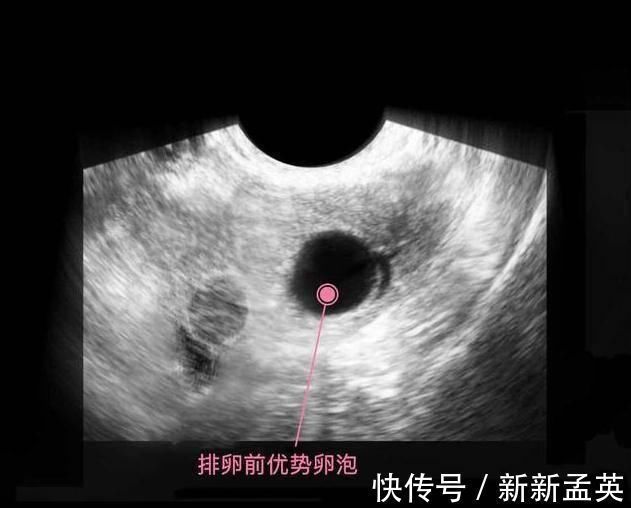

上图是第1周,卵子排出了优势卵泡,等待优质的精子冲破重重阻碍,卵子也不是一动不动,它从卵巢出来会用到输卵管里,在此等候精子先生12-24个小时,如果相遇,那么就结合成受精卵,受孕就成功了。